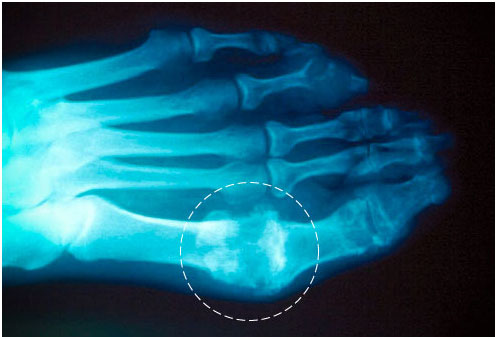

痛風(fēng)是一種常見且復(fù)雜的關(guān)節(jié)疾病,可導(dǎo)致關(guān)節(jié)極度疼痛和腫脹。引發(fā)痛風(fēng)的根本原因是體內(nèi)尿酸水平的升高,造成了尿酸鹽(痛風(fēng)石)在關(guān)節(jié)和腎臟部位的沉積。

痛風(fēng)發(fā)作相關(guān)的基因可能會影響60%的尿酸變化。研究人員發(fā)現(xiàn),SLG2A9、SLC22A12和ABGG2這3種基因跟痛風(fēng)有密切關(guān)系,人體內(nèi)這些基因組成不同,痛風(fēng)發(fā)作的概率可以相差兩倍。